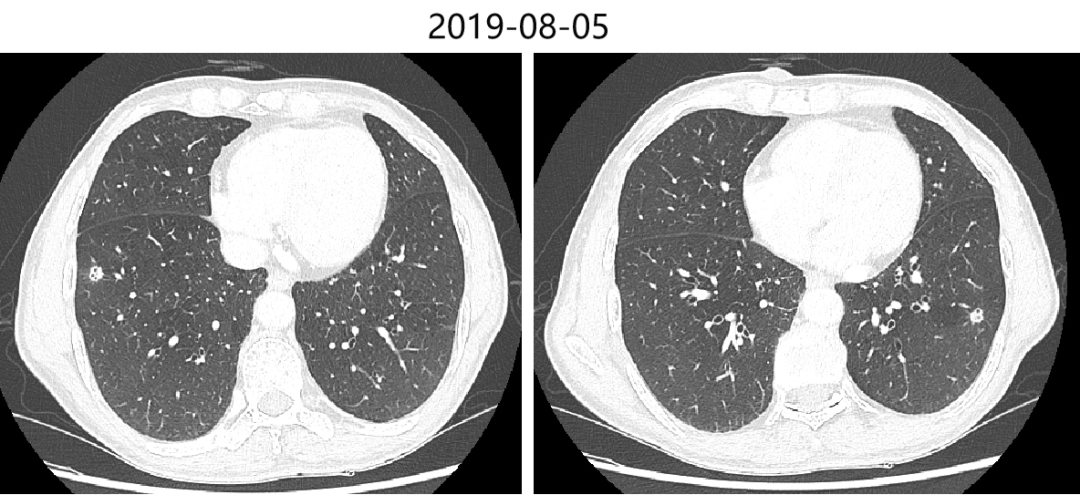

2019-08-05 胸腹部增强CT提示:双肺多发结节影,部分考虑转移可能,建议抗炎治疗后复查;双上肺肺气肿,多发肺大疱;脊柱胸段S形侧弯;胃术后改变;肝脏多发囊肿;肝左叶占位,考虑转移;胆囊结石;左肾小囊肿;前列腺钙化;直肠管壁局部增厚,考虑直肠癌可能,建议结合肠镜活检。

肺:双肺多发结节影,部分考虑转移可能。

肝:肝左叶占位,考虑转移。